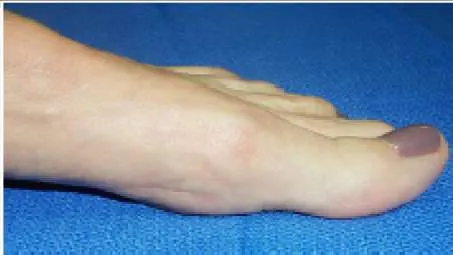

A 38-year-old woman presents for evaluation of painful hallux rigidus. Her clinical and radiographic images are shown (Slide 1 and Slide 2). Based upon her presentation, what is the likelihood that first metatarsus elevatus is responsible for her clinical condition:

Surgeons cannot assume that an elevated first metatarsal is responsible for causing hallux rigidus. On a lateral radiograph, there may be notable elevation of the first metatarsal (as present in this patient), but the elevation may be a secondary result of the limited motion of the hallux metatarsophalangeal joint. Studies have demonstrated that there is no difference in the elevation of the first metatatarsal in patients with hallux rigidus.

The patient shown in Slide 1 and Slide 2 underwent surgical correction of painful hallux rigidus. The purpose of the procedure on the hallux was:

Correct Answer: To elevate the hallux off the ground

The osteotomy of the proximal phalanx of the hallux (the Moberg osteotomy) is designed to elevate the hallux off the ground. The procedure does not improve the range of motion of the MP joint, but it increases the available motion of the hallux in toe off.